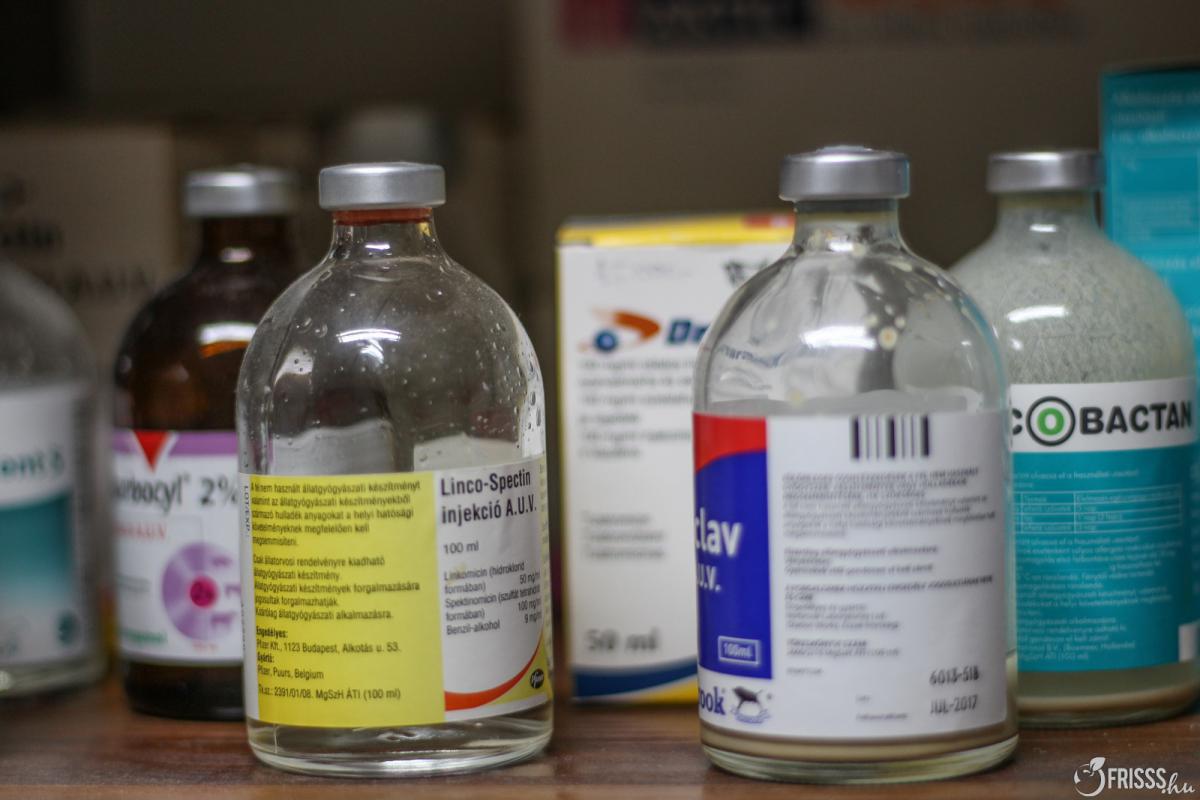

A zajfóbiával az a baj, hogy az idő előrehaladtával csak rosszabb lesz és egy gyengébb hanghatások is képesek kiváltani a pánikreakciót. Ezekre a szituációkra kínál megoldást a Sileo nevű szer, ami pont úgy hat a kutyára, mint emberre a Xanax. Ez az állatgyógyszer a szimpatikus idegrendszer aktivitását csökkenti, ami a gyakorlatban úgy néz ki, hogy a kutya megnyugszik, viszont nem fog zombiként viselkedni.

Fontos, hogy a Sileót még a tűzijáték kezdete előtt adjuk be a kutyának. Két-három órán át hat és maximum 5 adag adható egy nap. A szer egy gél, amit szájfecskendőből adagolhatunk a kutyánknak, csak a fogíny és a pofazacskó közé kell nyomni.